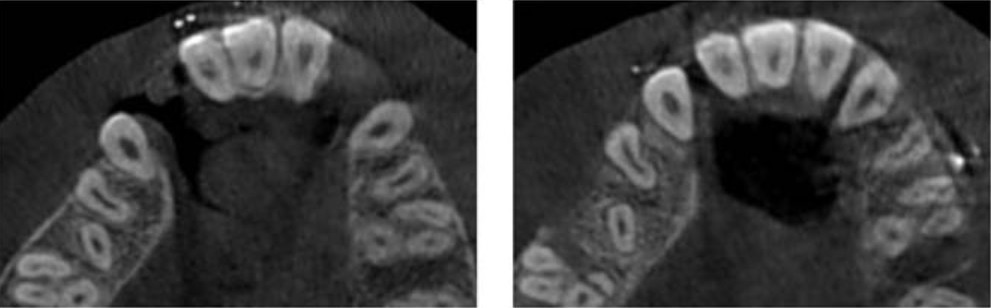

Tras dos semanas, se observa la reducción de las fisuras y la elongación de tejidos blandos, fijando los segmentos con ligaduras metálicas y manteniéndolos en contención por 4 meses. Un nuevo estudio con tomografía Cone Beam muestra avances significativos: la fisura derecha disminuye de 11,11 mm a 1,79 mm y la izquierda de 9,90 mm a 1,70 mm, con adecuada formación ósea en ambas zonas. Se detecta una lesión menor en la raíz palatina del primer molar superior derecho, sin comprometer la pulpa ni presentar complicaciones posteriores (Figura 3).

La reconstrucción 3D muestra buen contacto óseo y reducción completa de la fisura izquierda; en el lado derecho, falta tejido óseo radicular, pero el segmento se aproxima satisfactoriamente (Figura 4). En la comparativa de la reconstrucción 3D del lado derecho se observa la aproximación del segmento y la cercanía a nivel dental, sin embargo, debido a la anatomía que presentan los dientes adyacentes a la fisura y la cantidad de hueso alveolar en esta zona, es notable la falta de tejido óseo a nivel radicular para lograr mejor contacto (Figura 5). Del lado izquierdo se observa adecuado contacto a nivel óseo, dental y completa reducción de la fisura (Figura 6). Las fotografías clínicas confirman buena coloración, cobertura de tejidos blandos y reducción de la fístula palatina, logrando continuidad en el maxilar y cierre alveolar (Figura 7).